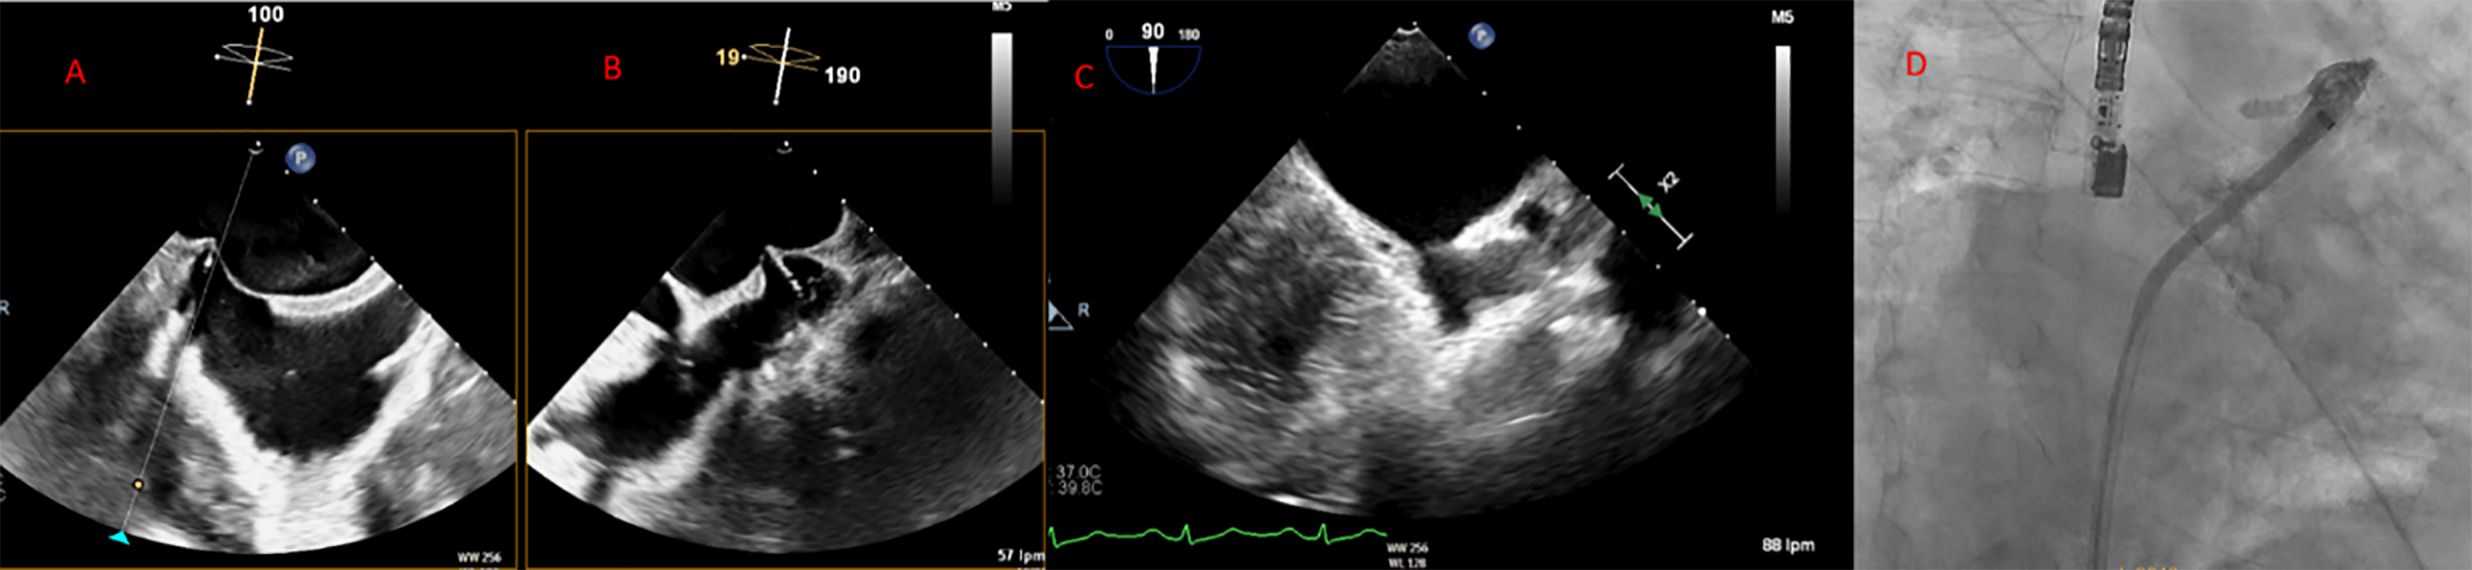

Fig. 5.

Transesophageal echocardiography (TEE) shows the tenting effect of the transseptal needle on the fossa ovalis in an inferior (left) and posterior (right) position.